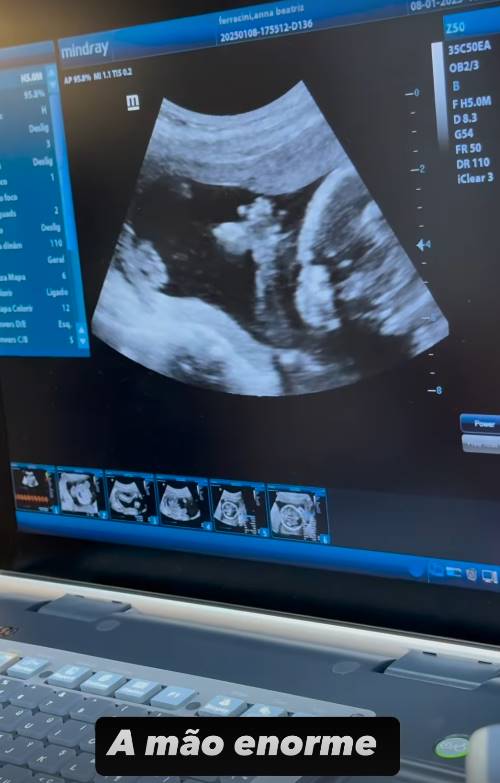

A influenciadora digital Bia Miranda, conhecida por sua participação no reality show ‘A Fazenda 14’, usou suas redes sociais recentemente para compartilhar um momento especial de sua gravidez com seus seguidores. Grávida pela segunda vez, fruto de seu relacionamento com Samuel Sant’Anna, Bia revelou detalhes de um exame de ultrassom realizado na quarta-feira, 8.

Durante a transmissão nos stories do Instagram, Bia mostrou o momento em que a médica apresentou as mãos e os pés do bebê. No entanto, apesar da ansiedade para descobrir o sexo do caçula, o bebê estava com as pernas cruzadas, o que impossibilitou a visualização do gênero.

A influenciadora expressou sua expectativa de estar à espera de uma menina. Caso o palpite se confirme, a filha irá se chamar Maysha. Bia brincou sobre o comportamento do bebê durante o ultrassom, destacando o quanto acredita na intuição de que se trata de uma menina: “Hoje tenho mais certeza ainda que é menina, para ser teimosa desse jeito…”.